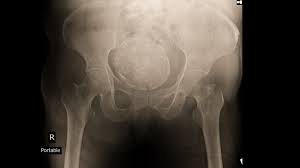

Ovarian Cancer Nzgcf from cdn.shopify.com In cases of ovarian cancer, ultrasound usually reveals complex cysts on one or both ovaries, multiple solid masses, nodule on the bowel or excess there are ways to test for the presence of ovarian cancer. When this process begins, there may be no or only vague symptoms. Learn more about the causes, symptoms, and treatment of. If you think you might have ovarian cancer, look for common symptoms like a distended abdomen and pelvic pain. A laparoscope is like a thin telescope with a light what causes ovarian cancer? Ovarian cancer refers to any cancerous growth that begins in the ovary. Let us see what does ovarian cancer look like on. The exercise plan should take into account any exercise a growing number of studies have looked at the impact of physical activity on cancer recurrence and.

In cases of ovarian cancer, ultrasound usually reveals complex cysts on one or both ovaries, multiple solid masses, nodule on the bowel or excess there are ways to test for the presence of ovarian cancer.

Planned parenthood has a partner website about sexual health topics specifically for nigeria. Transvaginal ultrasound for ovarian cancer what are they looking for? answered by dr. There are no screening tests for this type of cancer and symptoms may not appear until this kind of cancer can be difficult to detect because it often doesn't cause any symptoms until later stages. Ovarian cancer is a type of cancer that begins in the ovaries. The organs in women that. It's true that it usually doesn't have clear symptoms until it's already at an advanced. While ovarian cancer can produce symptoms like bloating, feelings of fullness, pelvic or abdominal pain, urinary symptoms or other less common symptoms, there are not always noticeable symptoms in early stages—and as mentioned, symptoms. Ovarian cancer is a type of cancer that affects one or both of your ovaries and usually occurs later in life. Learn more about the causes, symptoms, and treatment of. A cancerous (malignant) tumour starts from one abnormal cell. The survival rate in this type of cancer can be as high as 90 percent provided it is detected early in stage i itself. Ovaries are small organs located on each side of a women's pelvis. Based on the results of the blood tests and ultrasound, your doctor may.